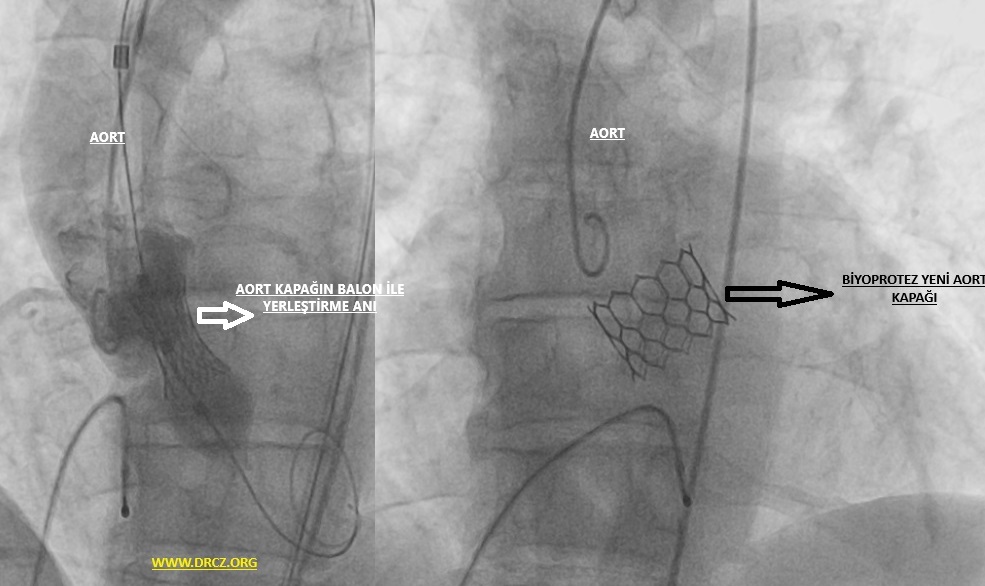

TAVI genellikle derin sedasyon ya da genel anestezi ile yapılan – kasıktaki atardamardan küçük bir kesi ile yapılan ağrısız bir işlemdir. Koroner anjiyografi veya stent işleminden kullanılan kateterlere benzeyen dar ve esnek bir tüp (katater)kasıkta bulunan atardamarınıza yerleştirilir ve kalbinizdeki aort kapağınıza ulaşılır. Bu kateter esnekliğini yitirmiş ve kireçli eski kapağınızın üstüne yedek bir kapak takmak için kullanılır. Bu katerterden geçen sistem ile ameliyata gerek kalmadan yeni biyoprotez kapak eskimiş kapağın üzerine yerleştirilir.

Resim 2: TAVİ' nin şematik görüntüsü.